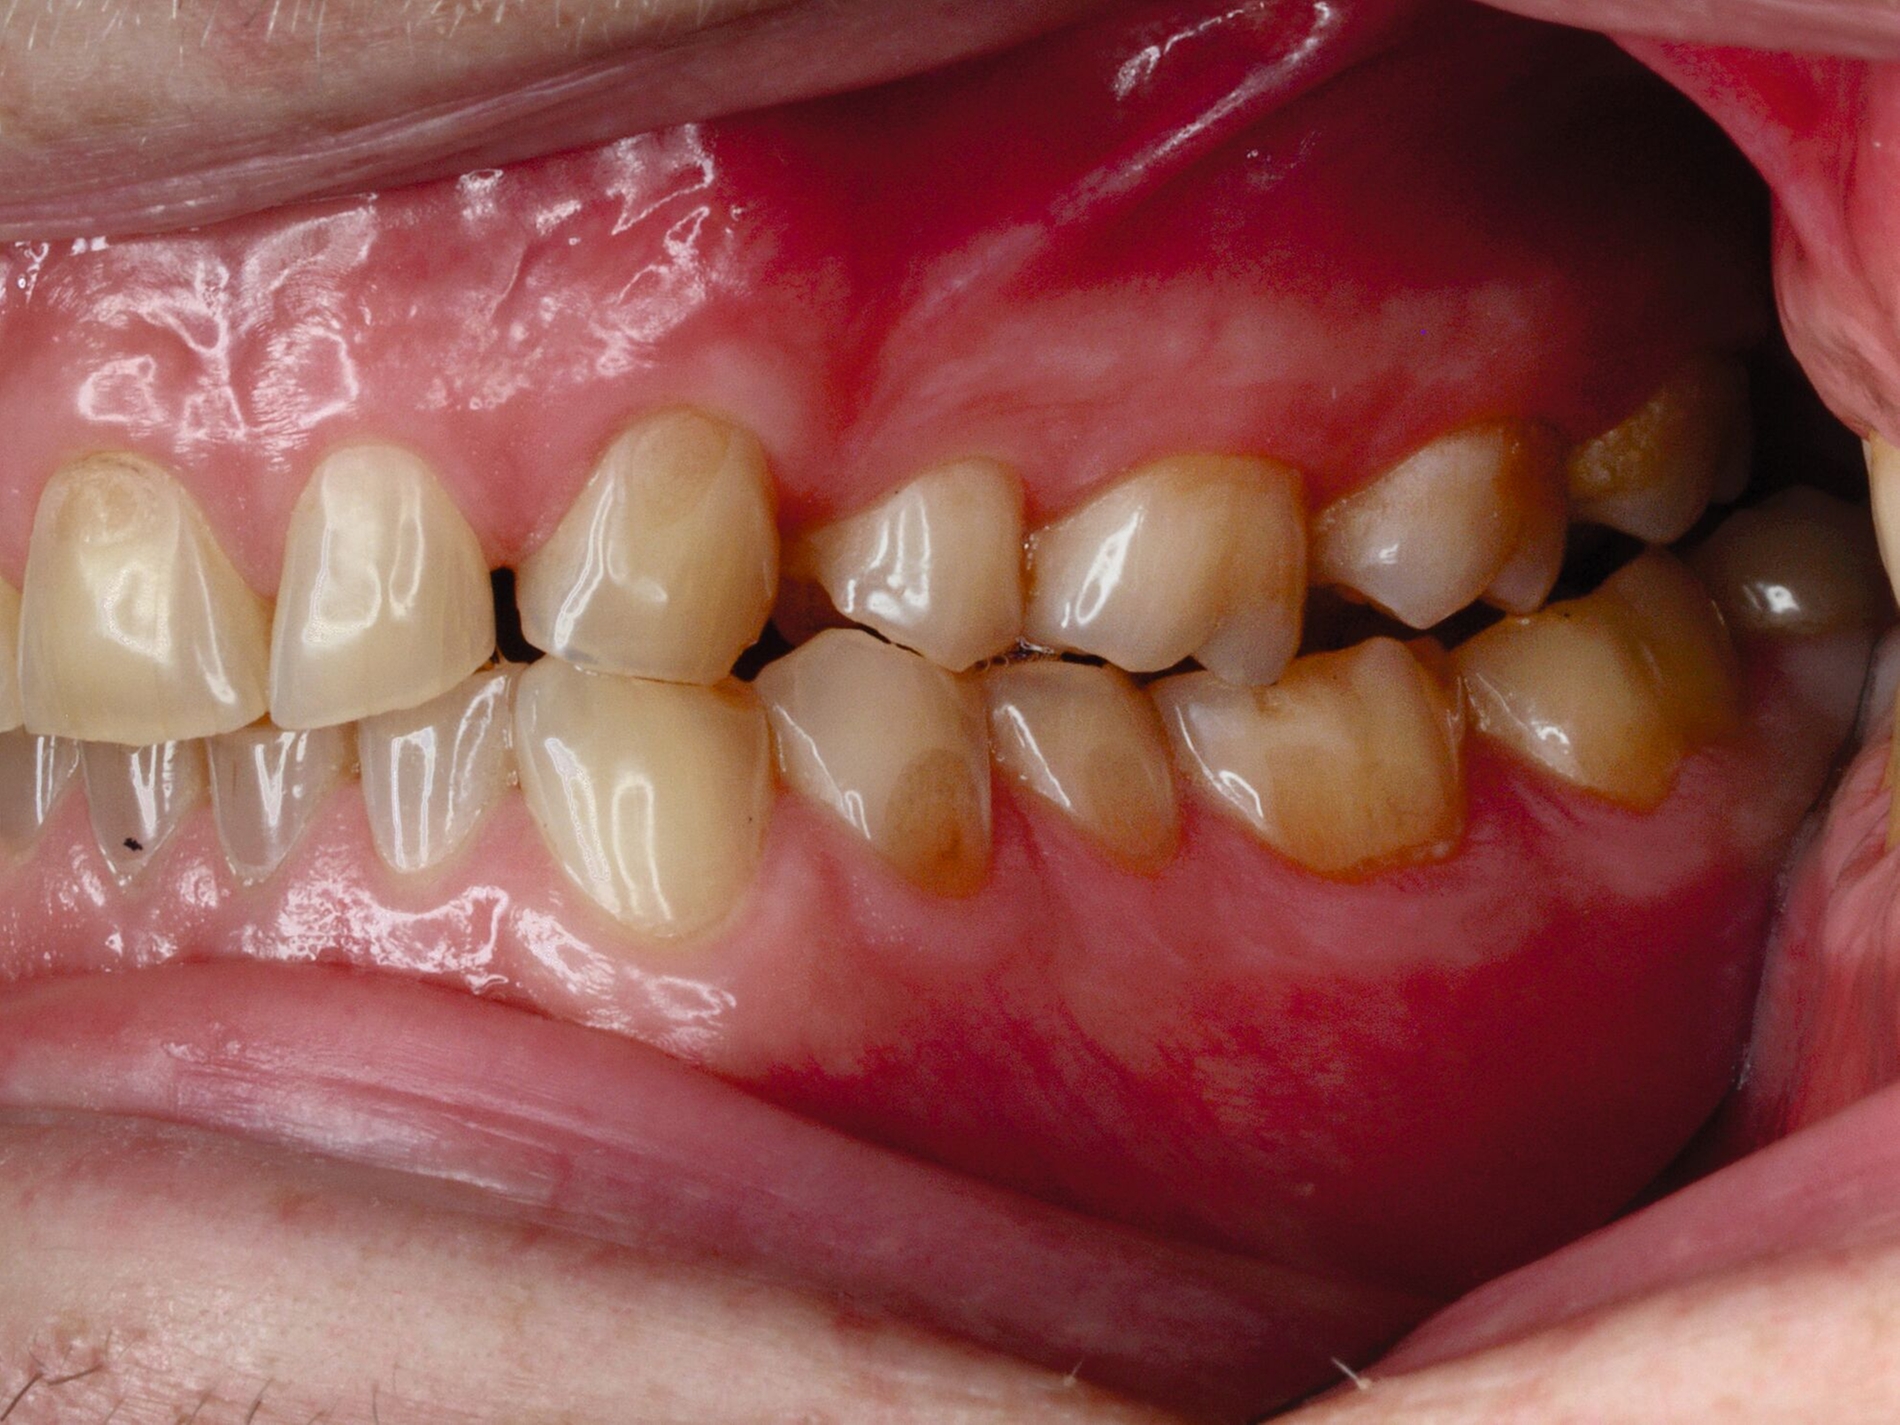

Das unter Beteiligung des Autors entwickelte Tooth Wear Evaluation System (TWES) 2.0 [Wetselaar et al., 2020] identifiziert per Screening Patienten mit erhöhten Verschleißwerten, vergleichbar mit dem PSI in der Parodontologie oder dem CMD-Kurzbefund. Bei auffälligen Werten folgt ein differenzierter Zahnverschleiß-Status einschließlich der Erfassung oraler und vestibulärer Substanzverluste [Wetselaar et al., 2016 sowie von Pathologie-Symptomen und einer strukturierten Diagnose [Tonetti und Sanz, 2019; Wetselaar, 2020]. Den Einsatz in der Praxis illustriert der in den Abbildungen beschriebene Patientenfall aus dem CMD-Centrum Hamburg-Eppendorf.

Im Unterschied zum Zahnverschleiß-Screening wertet der Zahnverschleiß-Status den höchsten Verschleißgrad pro Zahn aus, und zwar okklusal/inzisal, oral und vestibulär (Abbildungen 4b und 4c, Tabelle 1). Wichtig für die Planung therapeutischer Maßnahmen ist die Frage, welche Zähne okklusal in Kontakt stehen, denn die Behandlung von Zähnen mit erheblichem Zahnverschleiß lässt keinen weiteren Substanzverlust zu und erfordert bei Zähnen in Kontakt absehbar eine Erhöhung der vertikalen Dimension der Okklusion.

Im Beispiel ist daher die Diagnose ein generalisierter erheblicher und lokalisierter moderater pathologischer Zahnverschleiß überwiegend mechanischer und zudem chemischer Ursache. Die sich daraus ableitende Erkenntnis ist, dass in allen Sextanten Zähne freiliegende Dentinkerne aufweisen (generalisierter moderater Zahnverschleiß), dass darüber hinaus Zähne erheblich geschädigt und somit gefährdet sind, dass Merkmale eines pathologischen Geschehens bestehen – und dass als Ursache neben dem dominierenden Bruxismus ein Säureeinfluss hinzukommt.

Auch wenn Restaurationen nach Möglichkeit vermieden werden sollten, ist deren Verfügbarkeit für die Betroffenen individuell höchst wichtig, weil sie bestehende Schmerzen beseitigt, die verlorengegangene Kauleistung wiederherstellt und ästhetische und nicht zuletzt auch phonetische Einschränkungen aufhebt. Bei dem in den Abbildungen beschriebenen Fall korrelierte der erhebliche Zahnverschleiß mit der Lokalisation der Zahnschmerzen des Patienten. Direkte Restaurationen mit Kompositen hatten keinen Bestand. Die durchgeführte restaurative Behandlung hingegen hat Bestand, die Schmerzen waren danach umgehend verschwunden und sind seit zehn Jahren nicht wiedergekehrt.

Dabei führt die Verfügbarkeit hochfester Dentalkeramiken heute zu viel weniger invasiven Restaurationen als früher durchgängig übliche metallkeramische Kronen, und die Transluzenz der keramischen Werkstoffe ermöglicht zudem natürlichere Restaurationen. Der beschriebene Behandlungsfall zeigt, wie eine mehrstufige Zahnverschleiß-Diagnostik im Praxisalltag umgesetzt wird, mit initialem Zahnverschleiß-Screening und einer im Bedarfsfall erfolgenden erweiterten Diagnostik per Zahnverschleiß-Status.